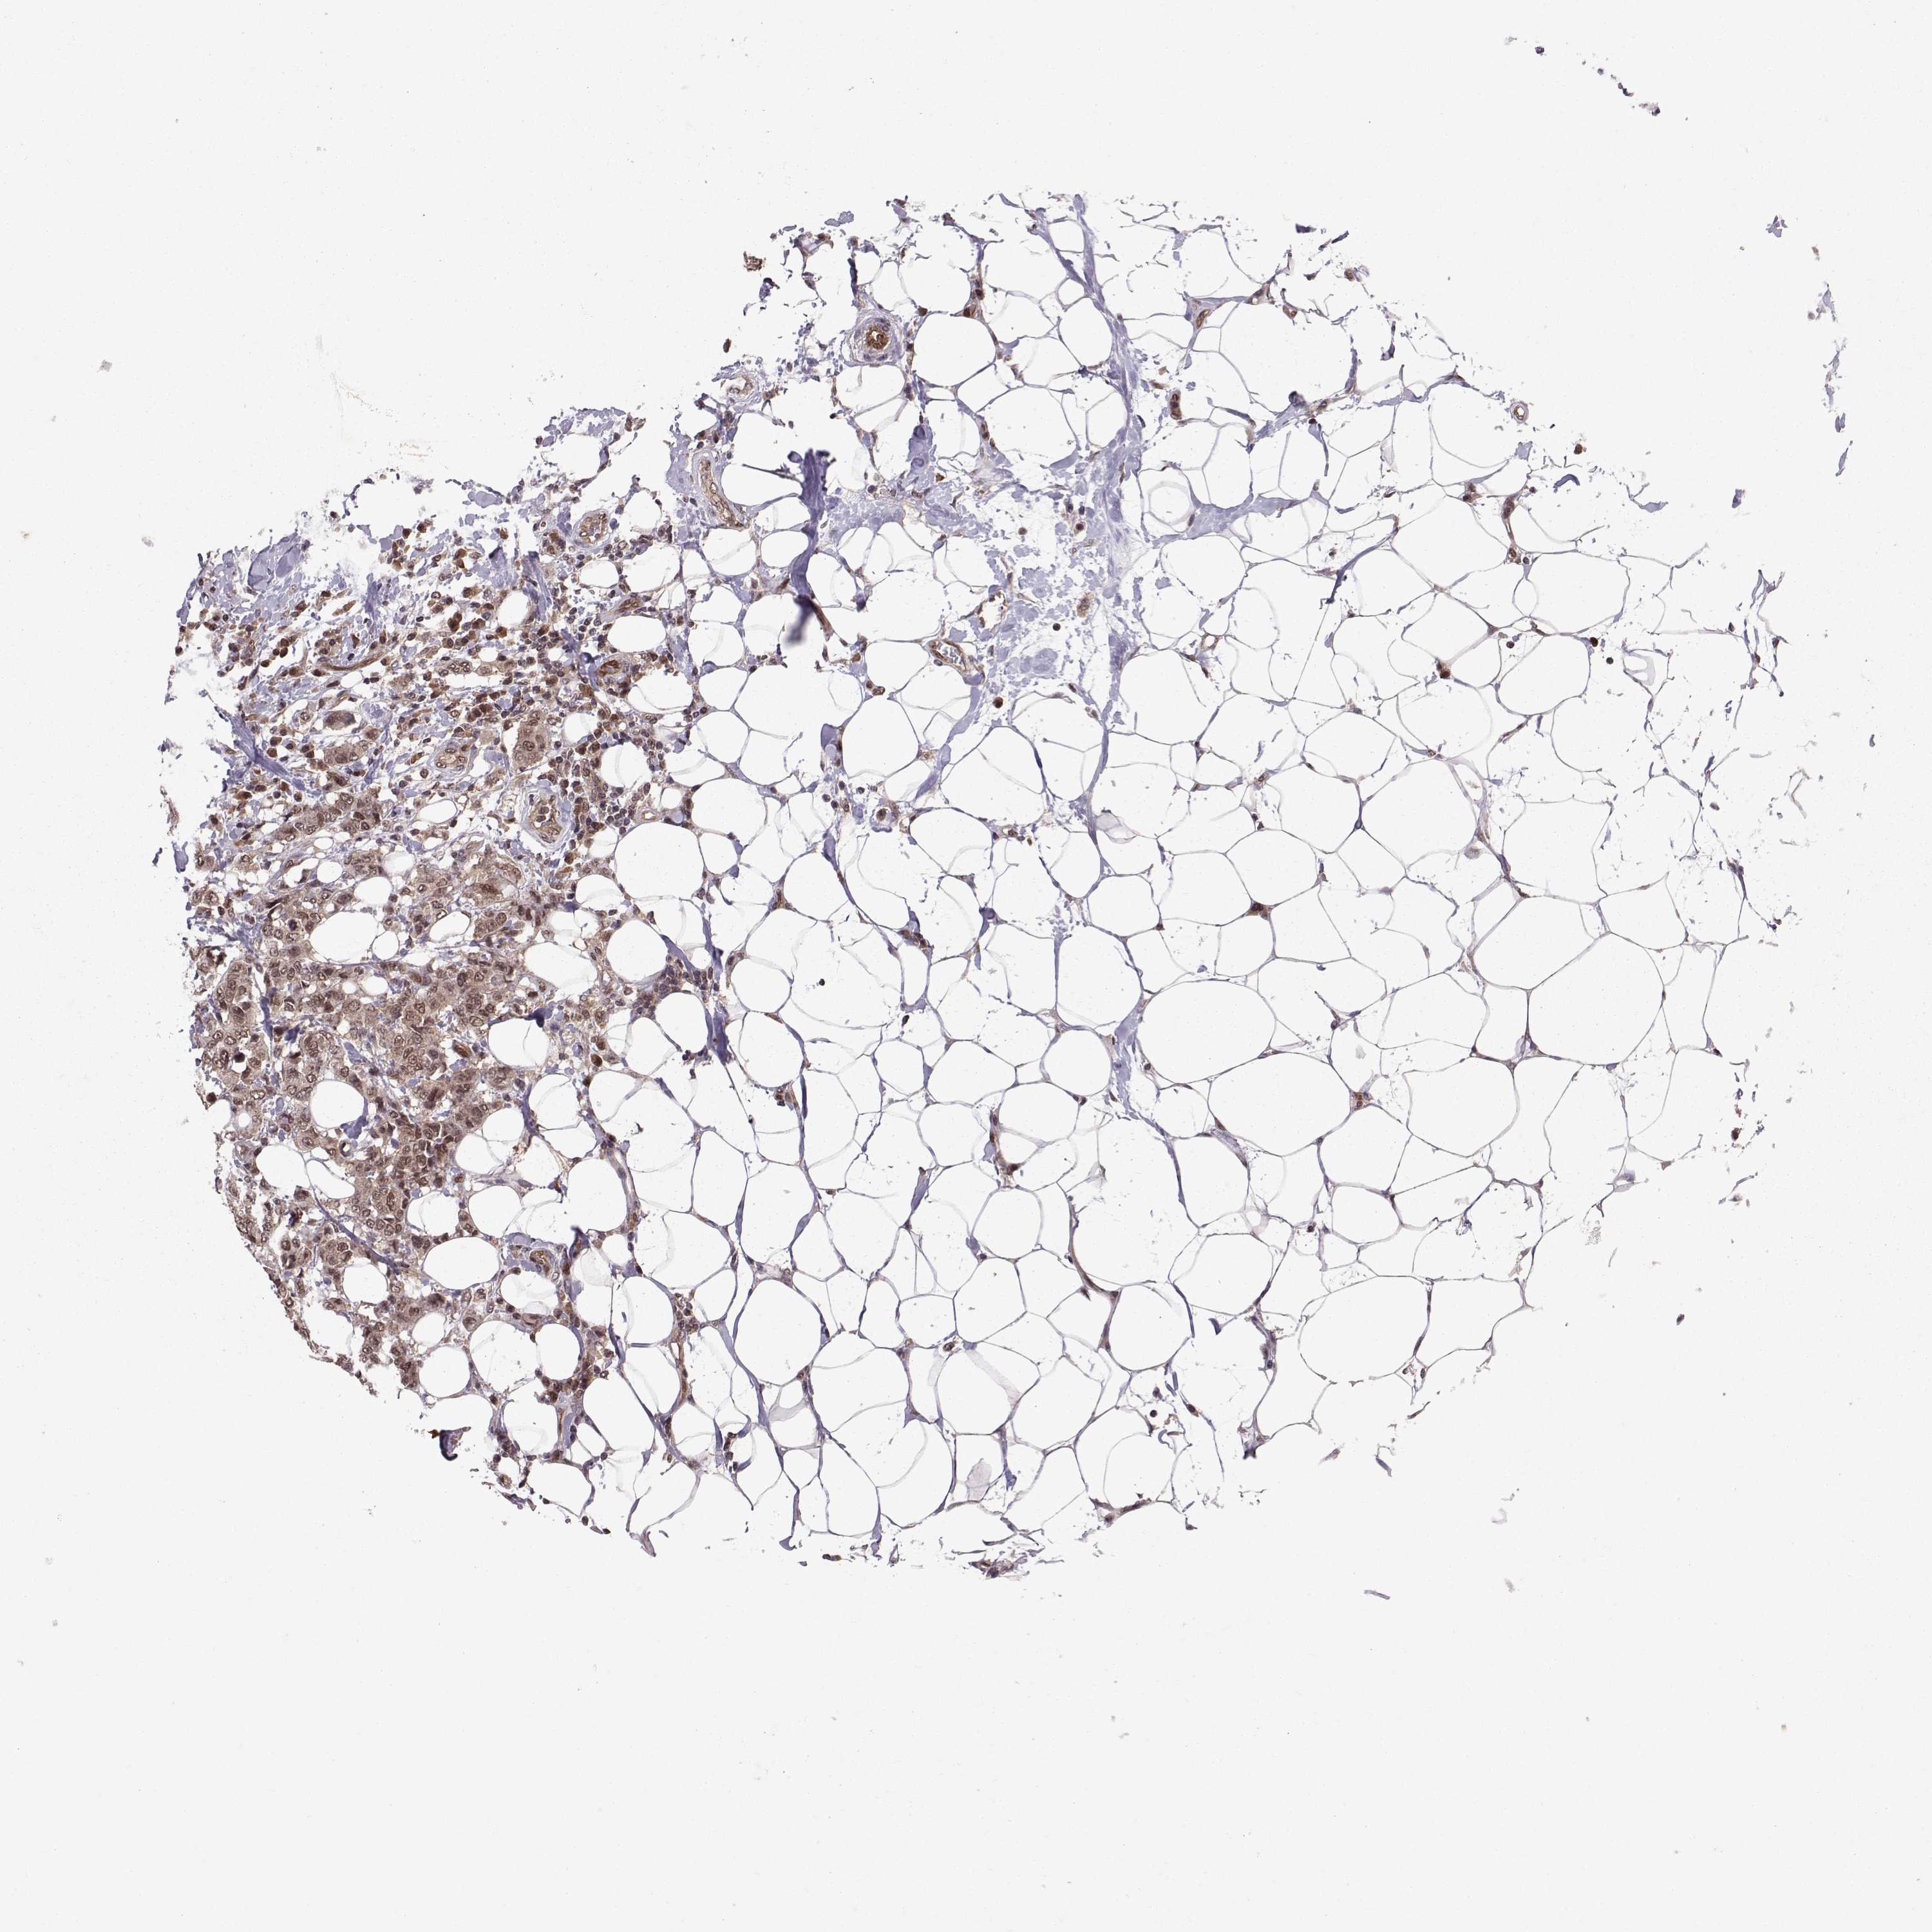

CANCER BREAST CANCER Show tissue menu

BRCA TCGA BRCA VALIDATION PROTEIN EXPRESSION